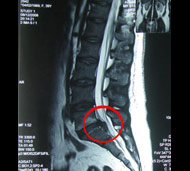

Чтобы определить, есть ли у вас межпозвонковая грыжа, врач соберет анамнез и проведет неврологическое обследование. В частности, он проверит симптомы, указывающие на сдавление нервных структур, а при их наличии исследует, насколько эти структуры потеряли свою функцию. Однако решающими в диагностике заболеваний позвоночника являются такие методы обследования, как:

- Магнитно-резонансная томография (МРТ). Для создания изображений вашего тела используется магнитное поле. Это исследование применяется для подтверждения локализации грыжи межпозвоночного диска и определения пораженных нервов. МРТ является золотым стандартом диагностики грыж межпозвонковых дисков.

Лечение грыж межпозвонковых дисков